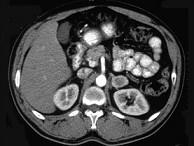

问题 女,34岁,无意中发现血压升高4个月就诊,行CT检查,如图所示,下列说法正确的是 ( )

选项 A、考虑为左肾上腺嗜铬细胞瘤 B、考虑为左肾上腺转移瘤 C、增强扫描,该病灶周边明显强化,中心处强化不明显 D、考虑为左肾上腺腺瘤 E、CT示左侧肾上腺区可见一等密度块影,边界清楚

答案 ACE